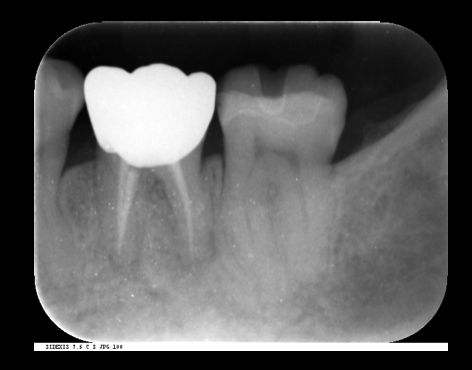

歯の根の治療(神経の治療)